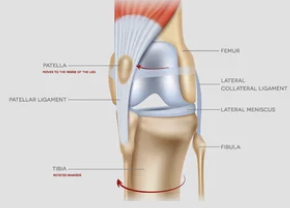

1️⃣ 슬개골 탈구란 무엇일까?

강아지의 무릎(슬개골)은 대퇴골 홈 안에 위치해 있어

다리 움직임을 안정적으로 도와주는 역할을 합니다.

하지만 이 슬개골이 제자리를 벗어나면,

관절이 어긋나면서 통증과 보행 이상이 생기죠.

💡 쉽게 말하면:

무릎뼈가 옆으로 ‘툭’ 빠지는 상태예요.